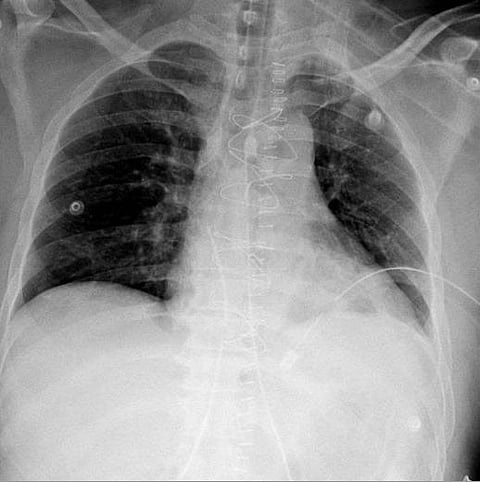

وأكدت الأشعة الصوتية وجود تجمع دموي حول القلب في تجويف التامور مع وجود استرواح هوائي حول الرئة اليسرى، ليتم نقله مباشرة إلى غرفة العمليات بواسطة الفريق الطبي المكون من استشاري الإصابات د. زيسس تولوميس، وزميل جراحة الإصابات د. أحمد فلاتة، وأخصائي الجراحة العامة د. أسرار الوادعي، ويترأسها استشاري ورئيس مركز الإصابات د. شرف الدين شودري.

وتم فتح صدر المريض من خلال عظمة القص، وتحرير القلب من الضغط المتكون من تجمع الدم في تجويف التامور، بعد ذلك تم التحكم بالنزيف وإصلاح عضلة القلب، وبتوفيق الله تحسن المريض وغادر العناية المركزة بعد يومين وهو بصحة جيدة.